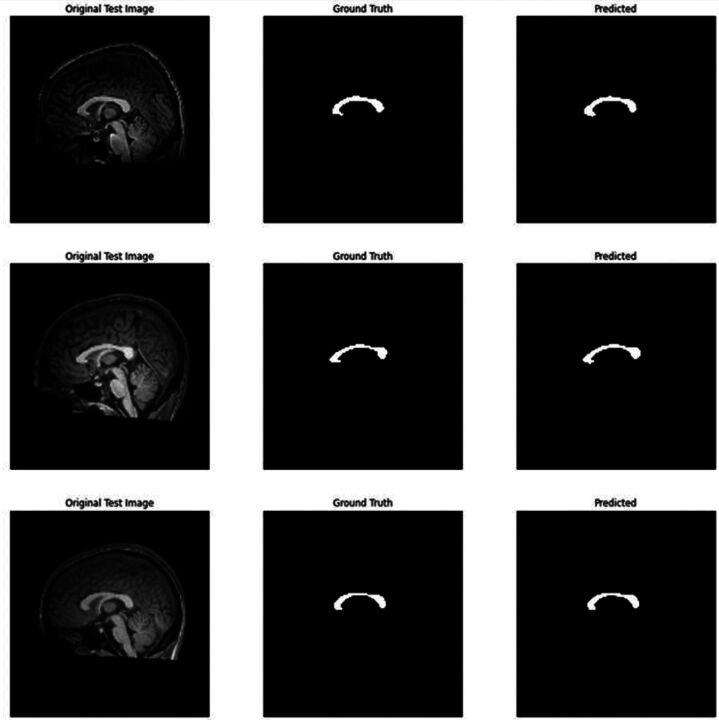

Methods: In this study, 150 MS patients (disease duration 12.6±5.9 years) and 150 healthy control subjects were scanned. Corpus callosum index was manually measured from the mid-sagittal slices on MRI. A deep learning architecture-based U-Net model was used for automatic corpus callosum segmentation from 2D brain MRI.

Results: The CCI score was calculated as mean 0.274 in the patient group and 0.382 in the control group (p=0.01). According to the ROC analysis, it was observed that the CCI measurement had a discrimination rate of 98.3% between groups with a cut-off value of 0.334. Sensitivity and specificity were calculated as 94%. The mean CCI calculated automatically after segmentation in the patient group was 0.286.